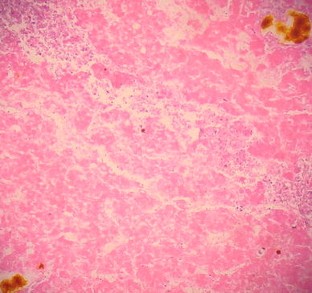

Fig. 1

Fig. 2

Fig. 3